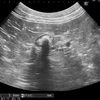

今回、同時に腹腔鏡補助下胃固定術を行いました。

今回は腹腔鏡補助下胃固定術を行いました。

画像は腹壁に固定した胃を内視鏡で確認しているところです。